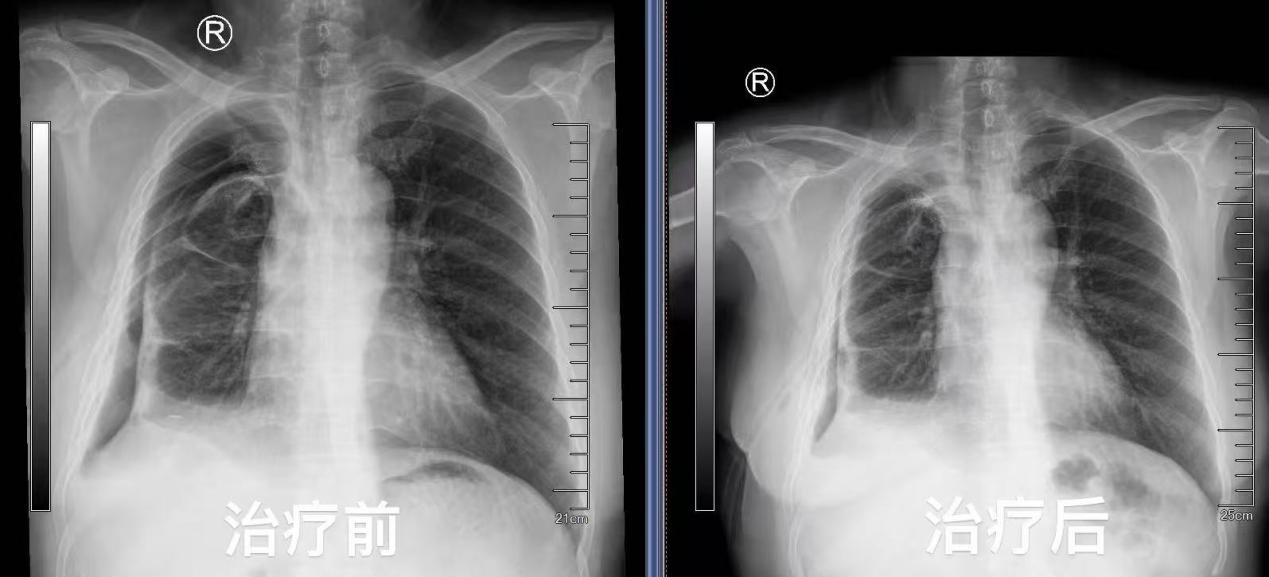

出院前复查气管镜于右上叶尖段见活瓣开口,局部予充分灌洗后未见气泡溢出,复查胸片提示右侧气胸较前明显吸收好转,困扰患者许久的胸腔闭式引流瓶终于得以拔除,王女士彻底告别了支气管胸膜瘘带来的阴霾。曾经,沉重的胸腔闭式引流瓶如影随形,严重限制了她的行动,如今,她终于能够轻松自在地行走。所使用的支气管内活瓣治疗也已纳入苏州医保,减轻了她的经济负担。出院之际,王女士难掩内心的感激流下了泪水,她紧紧握着蒋军红主任的手,言辞恳切地说到:“在患病的这段艰难日子里,是你们精湛的医术和无微不至的关怀,给了我重新生活的希望。每一次治疗,我都能感受到整个医疗团队的全力以赴。从病情诊断,到治疗方案的制定与实施,每一个环节都严谨细致,感谢蒋主任及各位医护人员。”